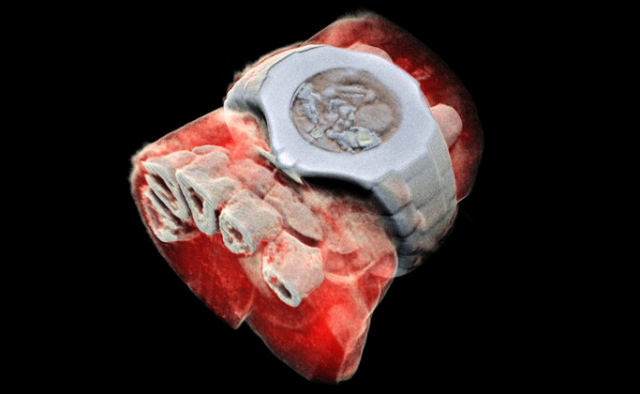

Медики впервые сделали рентген костей человека с трехмерными цветными изображениями. А примеры получившихся снимков можно увидеть на сайте новозеландской компании MARS Bioimaging.

Технологию придумали в семье ученых Батлер: отец работает физиком в университете Кентербери, а сын — рентгенолог в университетах Отаго и Кентербери. Основа рентгена в специальных детекторах с мощным энергетическим разрешением. Вообще они создавались для адронного коллайдера, но Батлеры приспособили их для медицинских целей.

«Сканеры MARS делают снимки, на которых можно различить мягкие ткани, жир и кости», — пишут ученые.

В первый раз цветной рентген протестировали на одном из его создателей — Филу Батлеру просканировали лодыжку и запястье. Теперь разработчики проведут клиническое исследование, в рамках которого врачи будут использовать и сравнивать новое и старое оборудование.